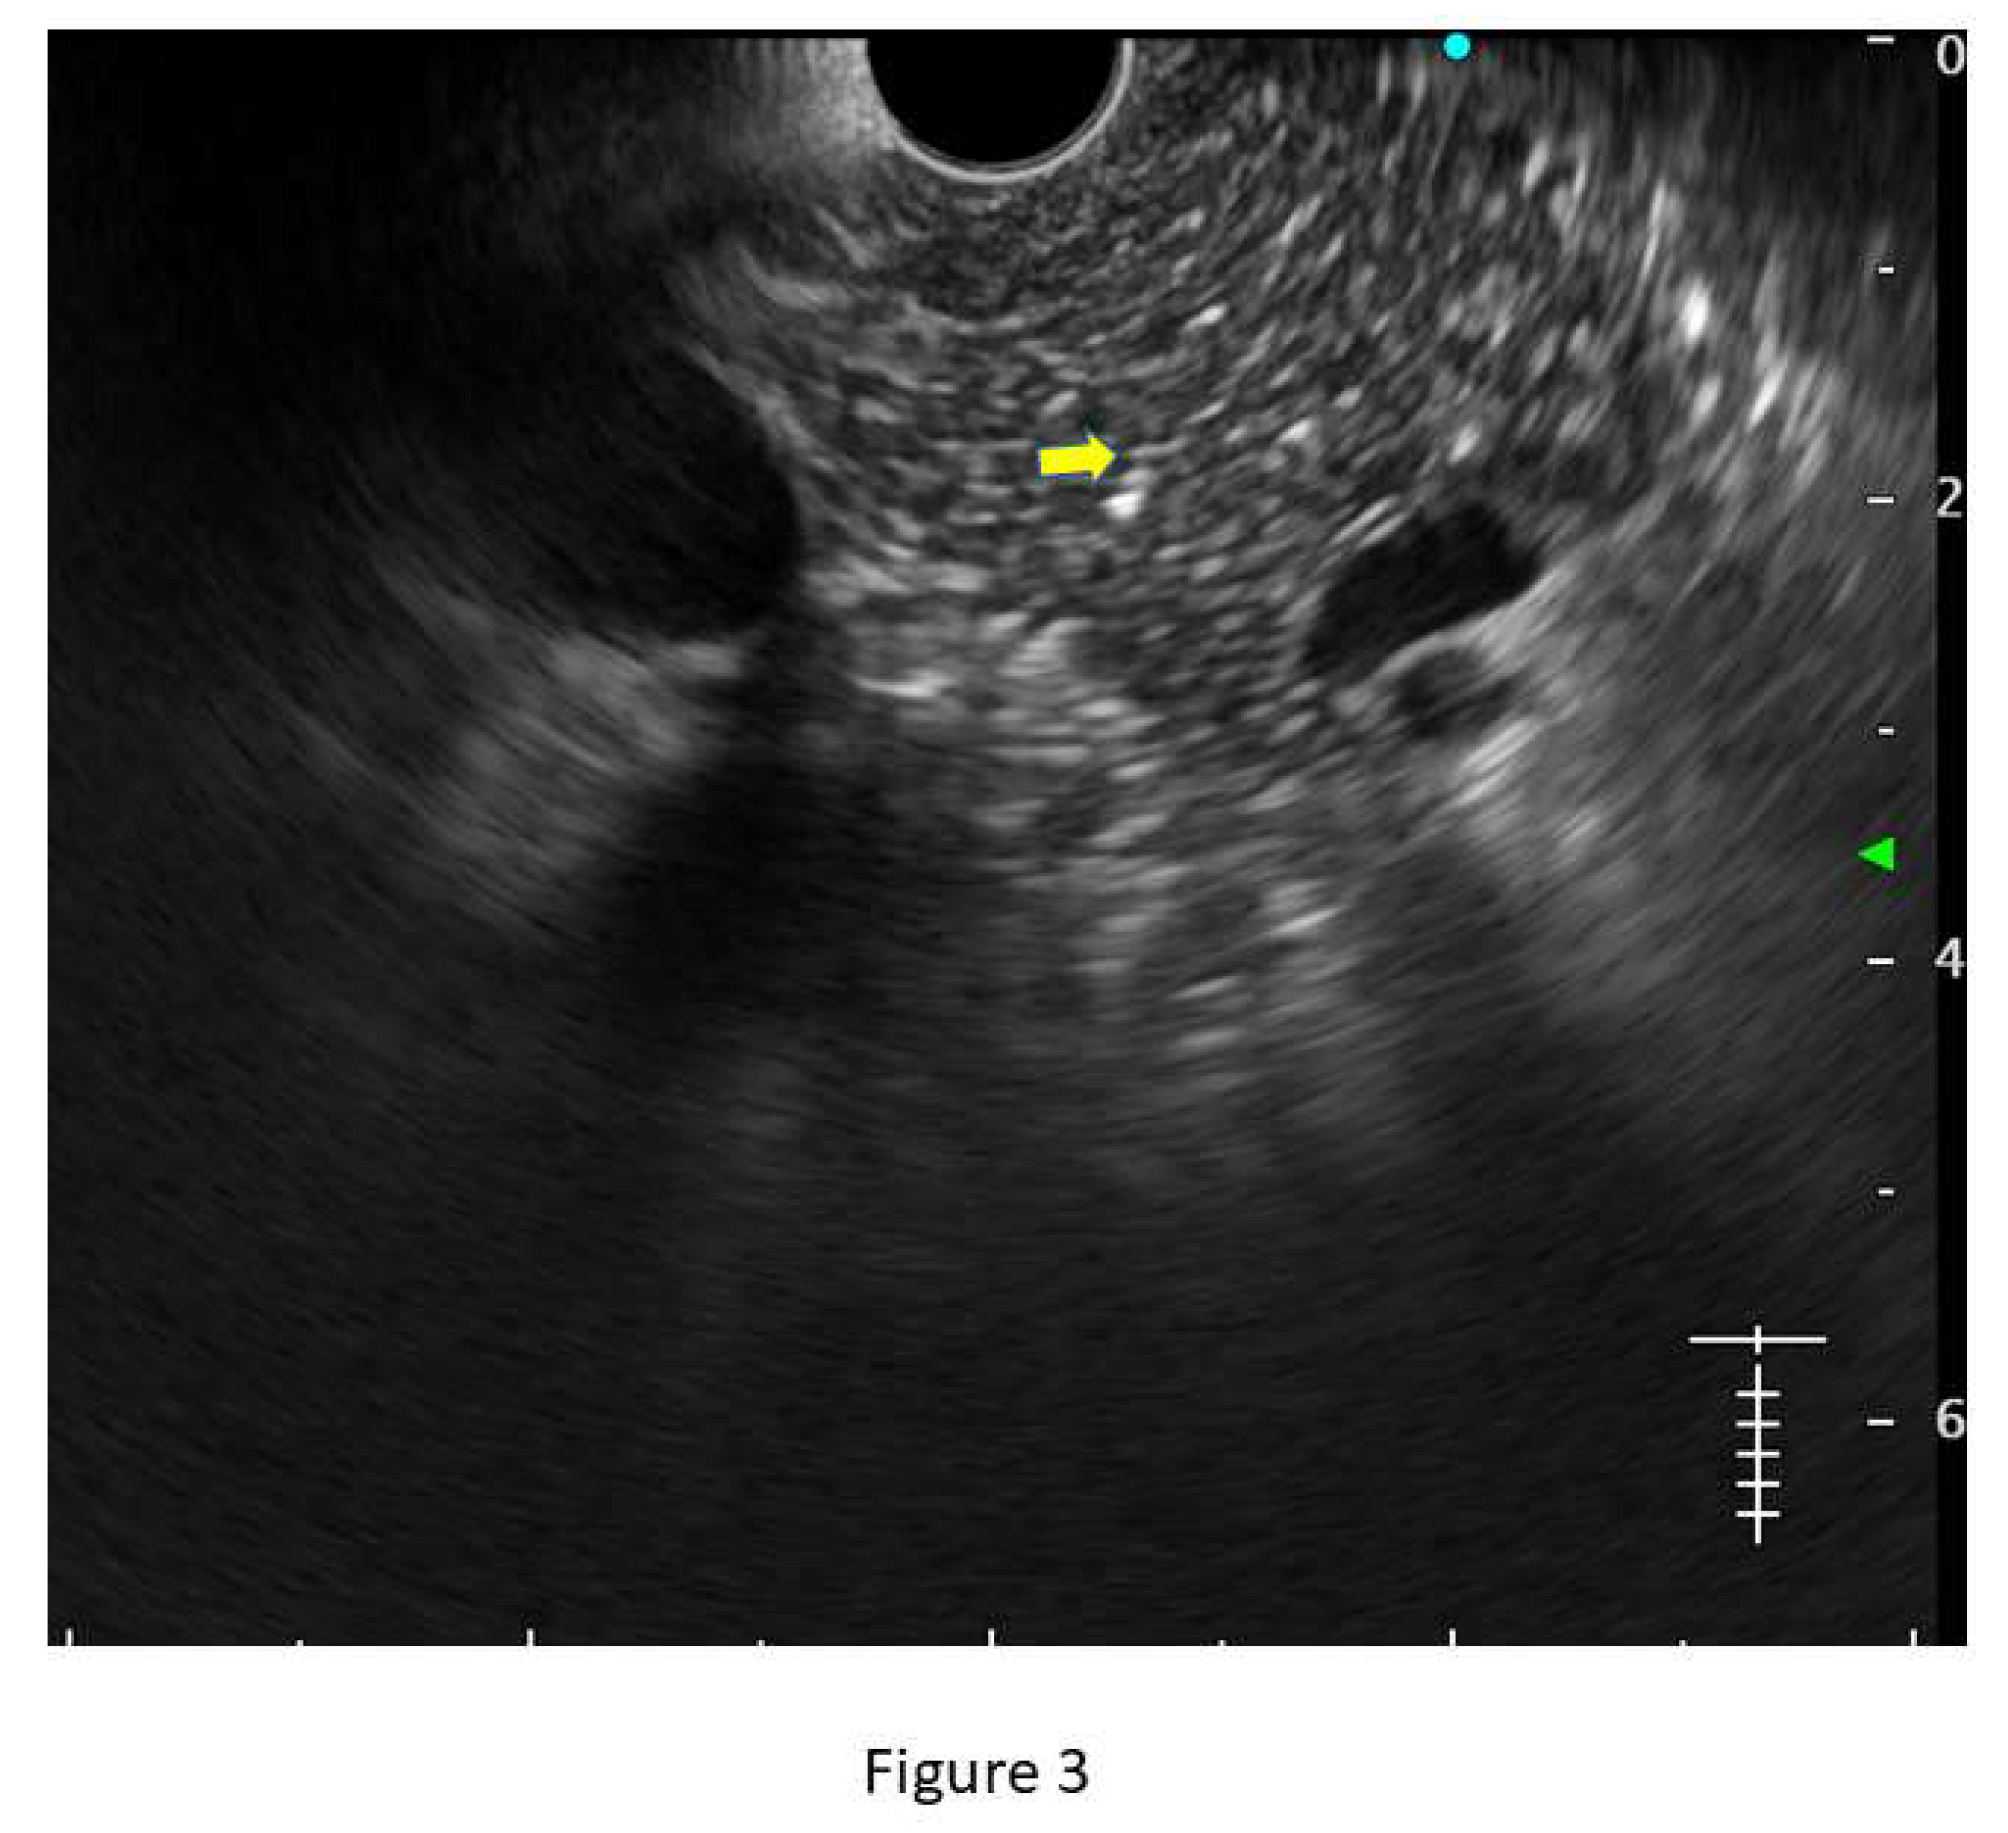

Figure 2. (a) Figure showing a lobularity without honeycombing (well-circumscribed reticulated areas, with a relatively hyperechoic rim) (b) Showing lobularity with honeycombing (three contiguous lobule yellow arrows) along with hyperechoic duct margins (green arrow).

• Lobularity with and without honeycombing: Lobules are described as well-circumscribed reticulated areas ≥5 mm in size, with a relatively hyperechoic rim compared to the adjacent central area. When these lobules are non-contiguous, the EUS pattern is described as ‘lobularity without honeycombing.’ When at least 3 of such lobules are contiguously located in the body or tail region, the pattern is defined as ‘lobularity with honeycombing’ in EUS. (32,33) (Figure 2) The exact histopathological correlation of lobularity is not precisely known. Studies however, have demonstrated lobularity to correlate with increased fat and collagen in biopsy specimens, and in a recent study, lobularity was demonstrated to be associated with increased disease severity, higher level of inflammation, and a trend towards higher grade of fibrosis and atrophy compared to absence of lobularity on EUS. (34,35)

• Hyperechoic margin of the MPD: It is described when hyperechoic ductal wall over at least 50% of the MPD is demonstrated in the body and tail of pancreas. In a linear echoendoscope, MPD assessment on a long axis is difficult. Thus, this finding is often subjective and has low interobserver agreement. (36) Histologically, they correspond to periductal fibrosis. In the study by Sekine et al, the hyperechoic MPD wall was described to correlate with thinning of the ductal wall on surgical specimens. (35) (Figure 2)